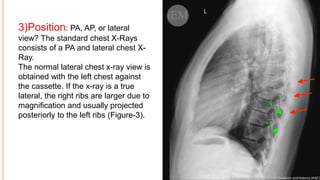

3)Position: PA, AP, or lateral

view? The standard chest X-Rays

consists of a PA and lateral chest X-

Ray.

The normal lateral chest x-ray view is

obtained with the left chest against

the cassette. If the x-ray is a true

lateral, the right ribs are larger due to

magnification and usually projected

posteriorly to the left ribs (Figure-3).

3)Position: PA, AP,or lateral view? The standard chest X-Rays consists of a PA and lateral chest X- Ray. The normal lateral chest x-ray view is obtained with the left chest against the cassette. If the x-ray is a true lateral, the right ribs are larger due to magnification and usually projected posteriorly to the left ribs (Figure-3).

• #23 The right ribs (red arrows) and left ribs (green arrows) on the lateral chest X-Ray.